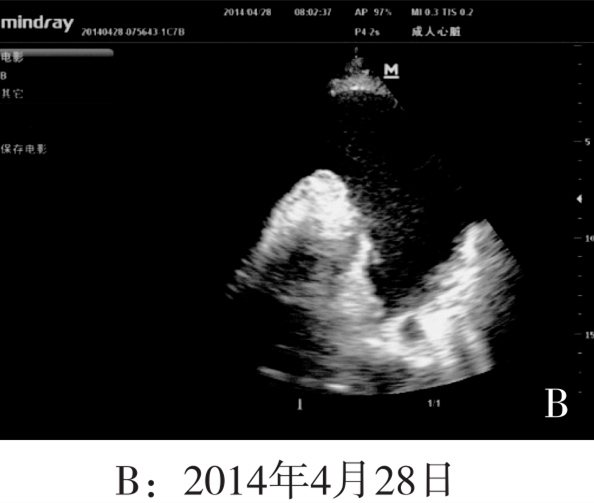

2014年3月14日:心脏彩超示如图A所示心包略厚伴少量心包积液,心尖处最深约0.8cm(光标划中本行显示超声结果)